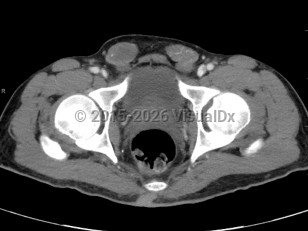

What is clear, however, is the general timeline for testicular descent, which proceeds in 2 phases. First, the testes migrate transabdominally during the first trimester and, by the 25th week of gestation, are usually located at the internal ring of the inguinal canal. The second phase, inguinoscrotal migration, requires androgenic signaling and is usually complete by 30 weeks. For this reason, premature males are at greatly increased risk of failed migration. Clearly identified risk factors for cryptorchidism include: